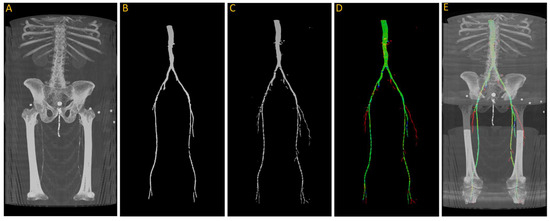

After training, we tested the first model with the “J2” data, and we generated a 3D reconstruction of the prediction, as shown in Figure 8. Figure 8A displays the input images used for the model; Figure 8B represents the ground truth; and Figure 8C shows the pixel-wise prediction obtained from the model. In Figure 8D, the predicted segmentation is overlaid on the ground truth, with blue regions indicating missed (false negative) segmentations and red regions representing incorrect (false positive) segmentations. On this test dataset, the model achieved a Dice accuracy score of 87.9% for segmenting the vasculature from the aorta to the femoral arteries.

Figure 8.

(A) Original input from patient J2; (B) ground truth; (C) predicted segmentation; (D) predicted segmentation vs. ground truth, where green is the intersection, blue indicating false negative, and red regions representing false positive; (E) overlaying (D) on (A).

From the visualization, we observe a significant decrease in the size of the region of interest (ROI) in the femoral arteries, along with some blockages in the main arteries. During the annotation process, small adjacent arteries were excluded when they lacked continuity with major vessels, but the model was able to detect some of these small arteries, resulting in a decrease in the reported accuracy. By comparing Figure 8A,E in detail, we can verify that the automatically segmented arteries flagged in red, specifically in the right leg, are actual arteries that were excluded in the annotation process.